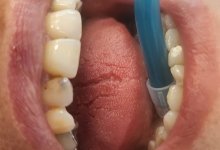

In urma unui consult dentar, medicul stomatolog stabileste primii pasi pentru implantul dentar: examen radiologic si analize de sange. La examenul radiologic se obtin informatii exacte despre cantitatea de os care urmeaza sa primeasca implantul dentar. Tot acum se poate stabili daca este nevoie de o eventuala aditie osoasa. Implantul se lasa in os intre 4 – 6 luni.

In acest timp are loc procesul de integrare in formatiunea osoasa. Succesul integrarii implantare este dat de catre formarea unei cantitati suficiente de celule osoase in jurul implantului dentar. In functie de necesitatile functionale sau estetice ale pacientului, urmeaza etapa protetica de realizare a lucrarilor de ceramica sau zirconiu. Implantul dentar este foarte important deoarece oasele maxilare se resorb, iar structura fetei incepe sa se modifice. In lipsa dintilor, atat masticatia cat si estetica au de suferit. O igiena necorespunzatoare, fumatul, bruxismul, etc., sunt factori de risc care duc la deteriorarea implantului. In perioada urmatoare dieta pacientului trebuie sa fie moale si la temperatura camerei.